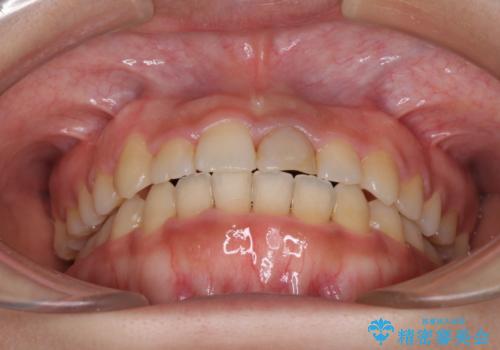

前歯の反対咬合 非抜歯のワイヤー矯正

1年半はかかると思っていた治療期間ですが、反対咬合となっている前歯が思いの外早く動き、僅か9ヶ月で終了させることができました。

前歯を気にせず笑えるようになり、患者様には大変満足していただきました。